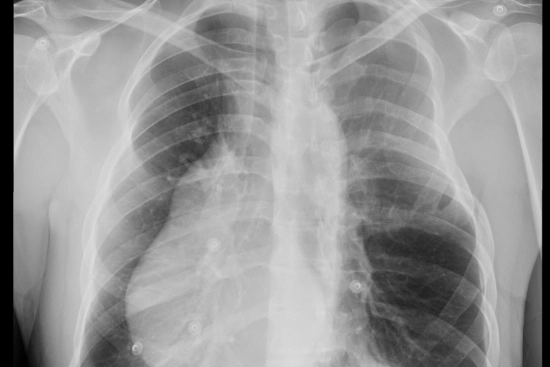

Struggling with chest asymmetry? This may be the result of Poland syndrome, a rare congenital condition that can affect self-confidence and body image. You don't have to live with it. Reconstructive surgery in Turkey offers advanced, personalized solutions to correct muscle underdevelopment, restore symmetry, and enhance overall well-being. With highly skilled surgeons and state-of-the-art medical facilities, patients can achieve natural-looking results and regain both comfort and confidence in their appearance.